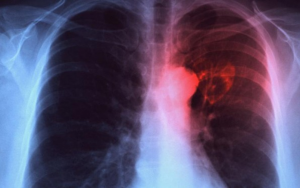

Rontgen dada

Foto thorak PA tampak gambaran bercak-bercak seperti awan dengan batas tidak jelas; pada kavitas berupa cincin; pada kalsifikasi tampak bercak padat dengan densitas tinggi